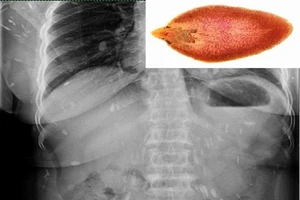

Hi hữu: Sán lá gan lổm ngổm chui ra từ ống mật

Đau thắt lưng, đi khám ra sán lá gan lớn sinh sôi khắp cơ thể

Sán lá gan làm tổ trong "của quý" vì thường ăn gỏi cá